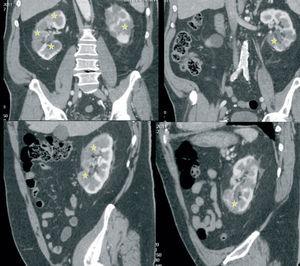

Due to the persistent abdominal pain and lack of concordance with digestive diseases, we performed an abdominal axial computed tomography that revealed segmental bilateral hypodense areas (Figure 1) with no lithiasis or dilation of the urinary tract. Together with the rest of the findings from examining the patient, this was suggestive of multiple renal infarctions, probably of an embolic origin.1

Figure 1. Abdominal axial computed tomography